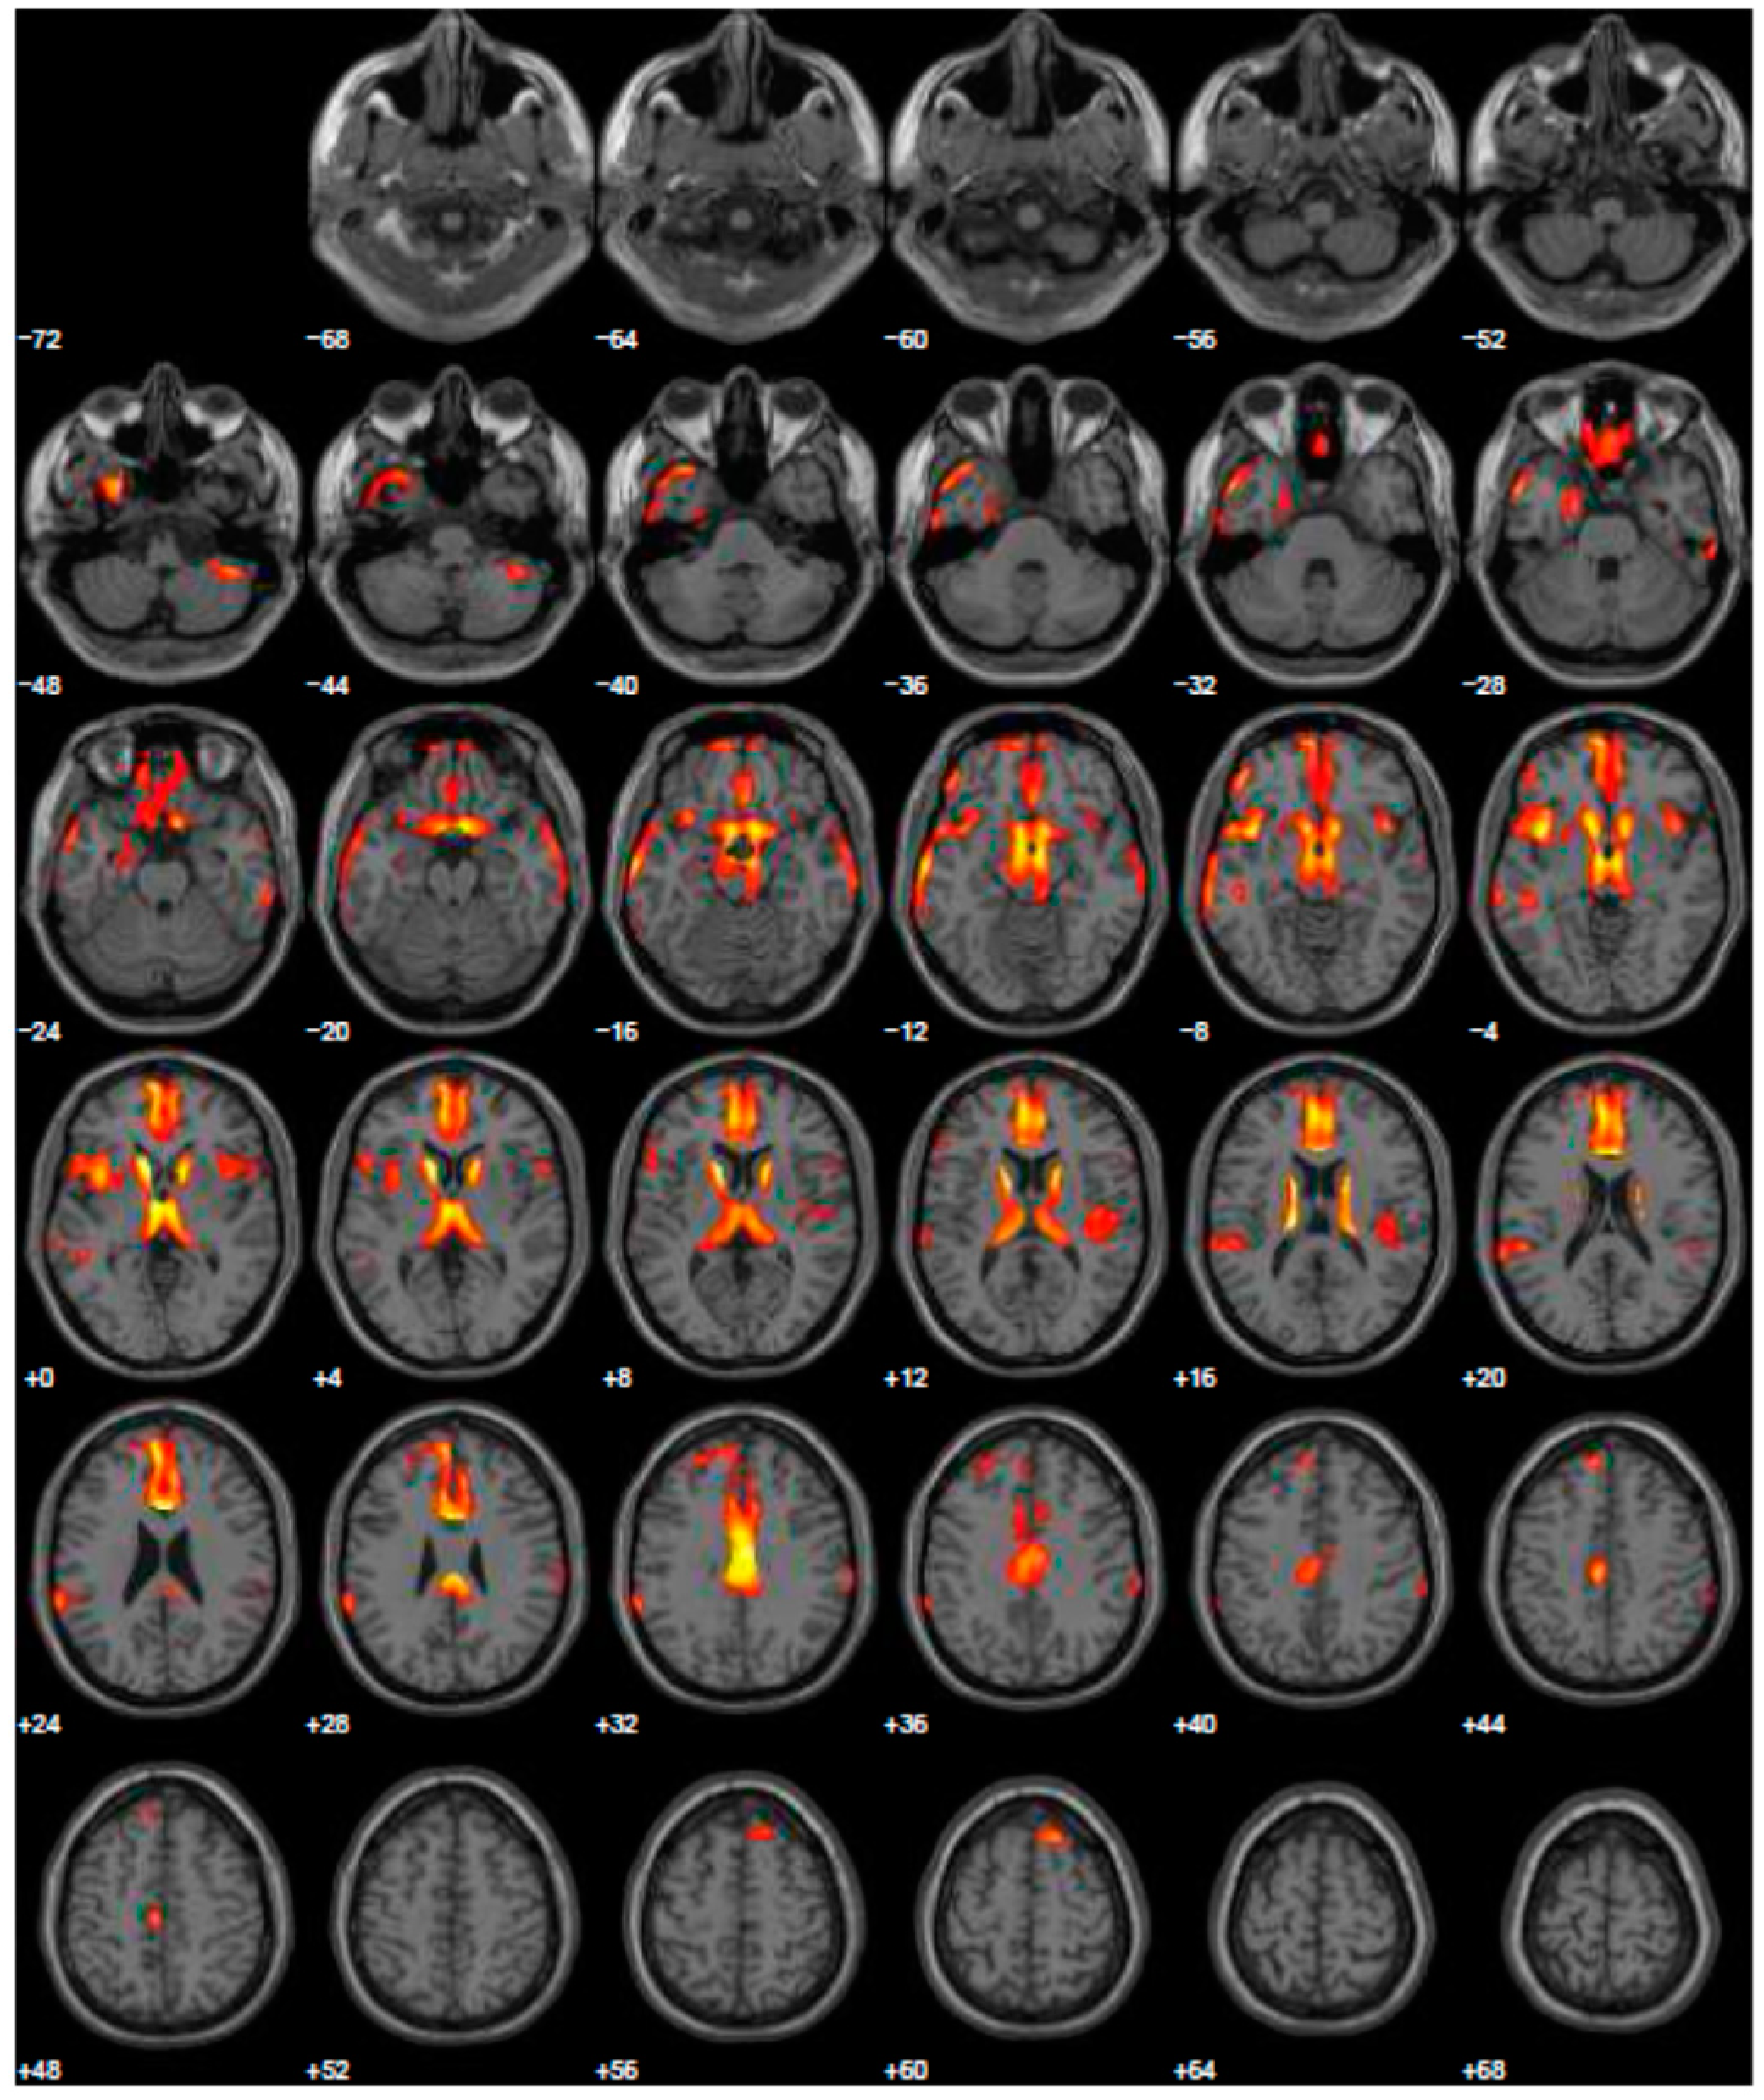

Given the reported ICDs, we changed treatment using L-dopa and prescribed the FDG-PET, to exclude other forms of parkinsonism. The FDG-PET scan showed hypometabolism in many cerebral areas involving, also in this case, the right and left inferior frontal gyrus and part of the prefrontal lateral areas (Figure 3). After the prescription of L-dopa at the dosage of 400 mg daily, we also added venlafaxine for improving depressive symptoms. After a 5-year follow-up period, the patient reported a discrete control of motor symptoms, e.g., he drove his car for more than two hours, and his wife reported a completely disappearance of ICDs, with significant improvement of behavior returning to the same as before starting treatment.

Figure 3.

Brain PET with 18F-FDG. Images highlight brain regions consistently found the analysis (Statistical Parametric Mapping software SPM 5 (p = 0.05). Hypometabolism in the left caudate body and head, left middle temporal gyrus, left superior temporal gyrus, right superior frontal gyrus, left and right inferior parietal lobule, left and right cerebrum sub-lobar insula, left and right superior temporal gyrus, left and right inferior frontal gyrus, right sub-lobar extra-nuclear gray matter, right cerebellar tonsil, right inferior temporal gyrus, left and right middle temporal gyrus, left limbic lobe uncus, left limbic lobe parahippocampal gyrus, right transverse temporal gyrus.